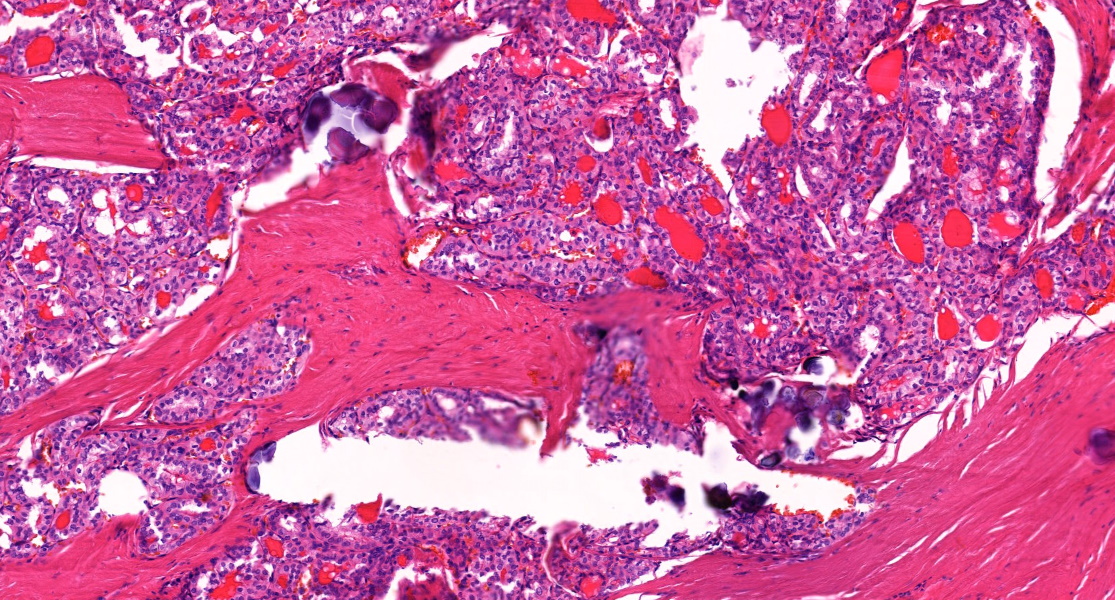

60+ female. Inguinal lymph node core biopsy. If you had to choose one diagnosis on H&E alone, what would you go for? #hemepath #pathology

Mark Ong tweet media